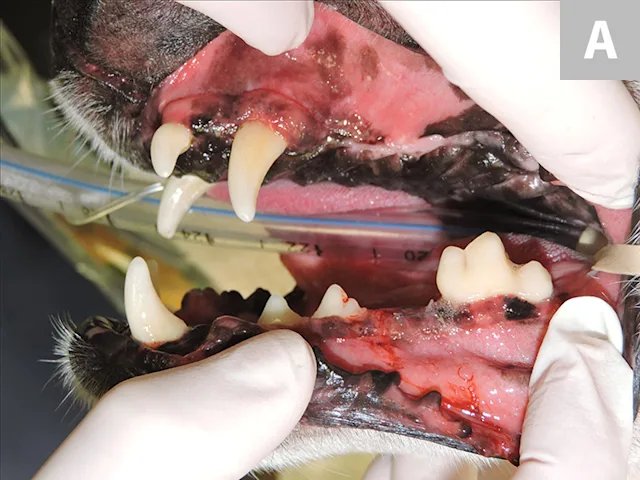

Close up of intubated dog mouth with periodontal probe pointing to oronasal fistula.

When operating in the oral cavity, general surgical principles should be applied to avoid dehiscence and/or formation of an oronasal fistula (Figure 5A). A common cause of oronasal fistula formation is extraction of a diseased maxillary canine tooth without a mucoperiosteal flap. Even if the canine tooth was diseased and easily extracted, flap closure of the extraction site is still indicated. Gentle tissue handling, tension-free closure, and a healthy environment for healing are essential to prevent flap failure at the surgical site. Adequate blood supply in the mouth is generally not an issue, but debridement of diseased bone and soft tissue are important to encourage rapid healing.

Figure 5A: Close-up of periodontal probe being inserted into oronasal fistula in a dog. Figure 5B: Close up of intubated dog mouth with periodontal probe pointing to oronasal fistula.

FIGURE 5

Oronasal fistula formation in a dog after extraction of the left maxillary canine tooth (A); closure of the defect was achieved with a single mucoperiosteal flap after debridement of the mature epithelium at the fistula edges. Chronic/recurrent oronasal fistula in a small-breed dog (B); closure of this defect required more advanced flap repair techniques.